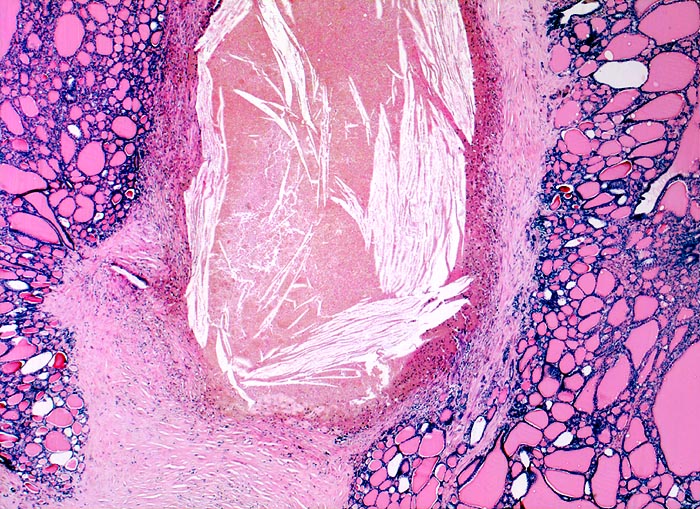

Knotenstruma mit regressiven Veränderungen

Hyperplasie / Hypertrophie

Schilddrüse

Unterschiedlich grosse Follikel. Dazwischen Stromafibrose mit alter Blutung (zahlreiche Cholesterinkristalle).

knotiges Schilddrüsenparenchym.

multinodöse euthyreote Struma mit szintigraphisch kalten Arealen